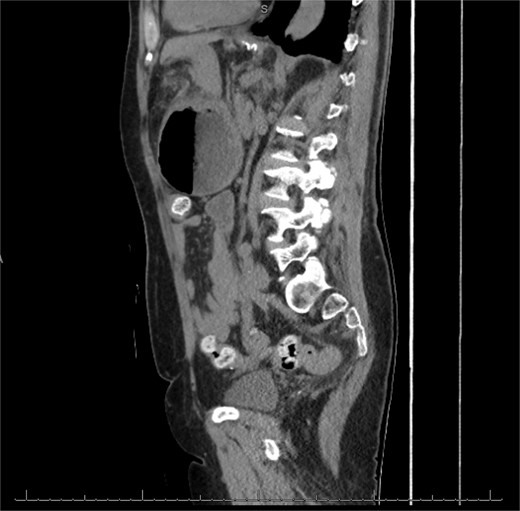

The patient was a 74-year-old female with a history of hypertension, chronic migraines, hiatal hernia repair with Nissen fundoplication repair, and cecal volvulus treated with right hemicolectomy who presented with abdominal pain, nausea, and vomiting. Six months prior, she exhibited symptoms of bloating and nausea, which were treated with oral Reglan with some improvement. She reported vomiting episodes for 2 months that acutely worsened over the 4 days prior to presentation. Examination revealed a soft and mildly distended abdomen with tenderness in the epigastrium and left upper quadrant. Initial vital signs showed a temperature of 36.1°C, blood pressure of 149/88 mmHg, heart rate of 115 beats/min, and oxygen saturation of 95% on room air; tachycardia resolved with resuscitation. Labs were notable for a white blood cell count of 8.8 × 1000/mcL and hemoglobin of 14.2 g/dL. Sodium was 137 mEq/L, potassium was 3.3 mEq/L, and creatinine was 0.75 mg/dL. Computed tomography (CT) of the abdomen and pelvis (Figs 1 and 2) showed gastric volvulus without pneumatosis, significant wall thickening, or distention. Nasogastric tube was placed. An upper gastrointestinal fluoroscopy scan showed no passage of contrast beyond the stomach and demonstrated 90° rotation of the stomach (see Fig. 3). The patient underwent surgery that same day.

Coronal view of CT scan of abdomen and pelvis demonstrating gastric volvulus.